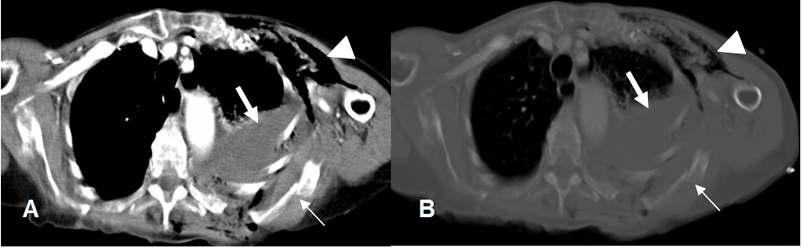

Fig 27 A. Fractura costal.

A: TAC axial en ventana de tejido y B: en ventana ósea. Fracturas costales múltiples en el lado izquierdo y de la escápula. (Flecha delgada). Hay hemotórax asociado (Flecha gruesa) y enfisema celular subcutáneo. (Punta de flecha).